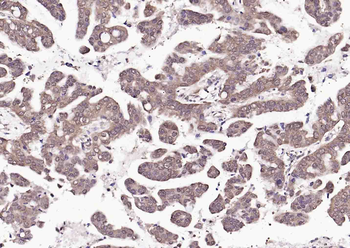

- PPM1D Rabbit Polyclonal Antibody [orb704535]Featured

IF, IHC-Fr, IHC-P

Human, Mouse, Rat

Mouse, Rat

Rabbit

Polyclonal

Unconjugated

100 μl, 50 μl, 200 μl - HSC70 Mouse Monoclonal Antibody [orb704174]Featured